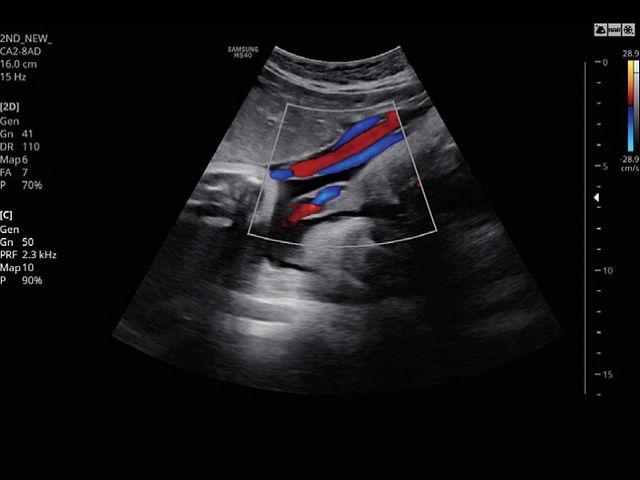

CA2-8ADApplication:Abdomen, Obstetrics, Gynecology, Pediatric, Musculoskeletal, Vascular, Urology, Emergency |